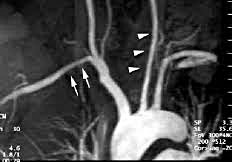

Синдром Такаясу на снимке

При УЗДГ сосудов, селективной ангиографии, аортографии выявляется частичная или полная окклюзия сосудистых ветвей аорты различной протяженности и локализации.

- Врачи обнаруживают неспецифический аортоартериит посредством ангиограмм. Ангиограммы — это виды рентгенологических исследований, которые показывают артерии. При артериите Такаясу ангиограммы показывают сужение крупных артерий.

Врачи чаще всего обнаруживают болезнь Такаясу при проведении ангиограммы, которая показывает, насколько хорошо кровь течет в артериях.

Существуют различные типы ангиограмм, в том числе стандартные, которые включают инъекцию красителя непосредственно в артерию во время проведения рентгенологического исследования.

Менее инвазивные типы ангиографии используют другой метод визуализации, такой как компьютерная томография, и называется КТ-ангиография или КТА.

Когда используется МРТ — магнитно-резонансная томография — это называется магнитно-резонансная ангиография или МР-ангиография, МРА.

Ангиограммы могут показать сужение одной или нескольких крупных артерий. Для доктора важно различать сужение из-за васкулита (воспаление артерий) и сужение из-за атеросклероза («затвердение» артерий). Иногда это может быть сложно. Есть и другие причины артериального сужения, в том числе фибромышечная дисплазия, еще одно редкое заболевание, которое в основном поражает женщин.

При офтальмологическом обследовании отмечается снижение остроты зрения, чаще одностороннее, и выпадение полей зрения. Патология со стороны глазного дна встречается более чем у половины больных. Выделяют 4 стадии ангиопатии. В первую — наблюдается дилатация мелких сосудов, во вторую — образование аневризм, в третью — формирование артериове-нозных анастомозов, в четвертую — сосудистые осложнения. При развитии артериальной гипертензии наблюдается типичная картина гипертонической ангиопатии сетчатки. Одним из основных инструментальных методов обследования больных с артериитом Такаясу является ангиография. Ее результаты имеют важное значение как для подтверждения диагноза, так и для оценки динамики и распространенности воспалительного процесса. [M.Yamato et al, 1986; J.Jackson, D.Allison, 1994]. Ангиографическое обследование позволяет оценить степень развития коллатерального кровообращения и состояние сосудистого русла дистальнее участка стеноза или окклюзии сосуда. Это особенно важно при поражении брахицефального ствола, легочной артерии, коронарных и подключичных артерий. Недостатком этого метода исследования является то, что он характеризует только степень сужения или дилатации сосудов, но не выраженность изменений в самой сосудистой стенке [S.Hall et al, 1990] В последнее время все большее значение приобретают неинвазивные методы, включая ультразвуковую ангиодопплерографию, компьютерную и магнитно-резонансную томографию [Р.А.Хорошаева, 1992; А.В.Прокопенко, 1995; K.Tanigawa et al., 1992; R.Raninen et al., 1996]. В некоторых случаях, при отсутствии стенозирующих и/или окклюзивных процессов в аорте, ее крупных ветвях, легочной артерии, эти методы позволяют установить диагноз на ранней стадии заболевания, когда наблюдается лишь снижение оптической плотности пораженного участка сосуда, утолщение сосудистой стенки, появление феномена двойного контура и нарушение ламинарного потока крови. Выявлена низкая чувствительность сканирования сосудов с использованием меченных индием-111 лейкоцитов для диагностики активности васкулита [C.Chen et al., 1995].

В то же время предварительные результаты свидетельствуют о возможности количественной оценки воспалительных изменений в сосудистой стенке с помощью магнитно-резонансной томографии [S.Fram et al., 1996].

Хотя традиционная ангиография исторически была стандартом для диагностики и оценки степени заболевания, методы компьютерной томографии и магнитного резонанса получили преимущество для первоначальной оценки, поскольку они менее инвазивны, чем стандартная ангиография, и позволяют диагностировать артериит Такаясу на ранних стадиях заболевания. Ультрасонография полезна для оценки сонной артерии, тогда как позитронно-эмиссионная томография 18F-фтордезоксиглюкозы (18F-FDG-PET) полезна для пациентов без сосудистых признаков или симптомов, лихорадки неизвестного происхождения или необъяснимого ответа острой фазы.